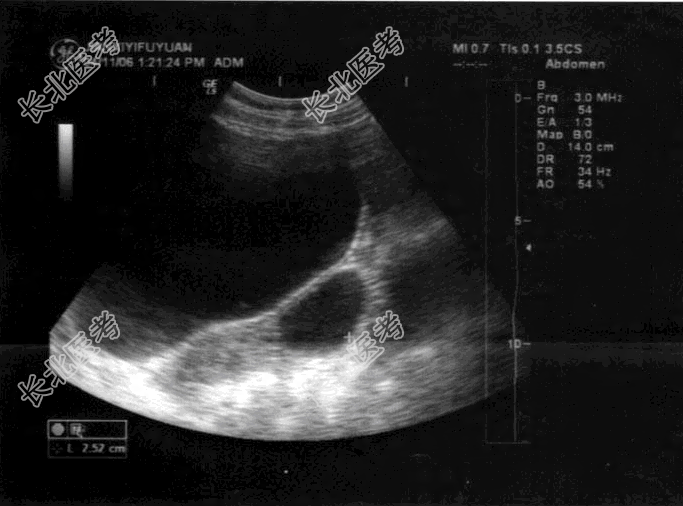

- 单项选择题女,25岁, 超声检查如图,最可能的诊断为

A、左卵巢癌

B、左侧输卵管积液

C、左卵巢卵泡

D、左卵巢囊肿

E、扩张的左侧输尿管